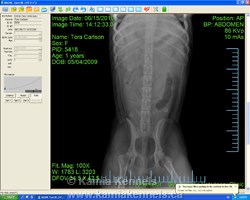

Tora, hip x-ray - perfect set

If you have never seen a perfect set of hips before, you can say you have now, I should have put this up before but, you know how it is you get busy. Tora has a set of ball sockets you could write a book on. She is a pretty amazing female, no doubt about that. We are not big proponents of x-rays and such, but she was in for a check up and I asked for our vet to do a set so I could see them, I knew her hips were perfect long before I took this, I didn't take this for any reason other than curiosity really. Neat to see though isn't it.

People sometimes ask about hips, not sure why, Elkhounds don't have any issues with hips to speak of, I can't say I have ever even heard of an Elkhound with a hip problem, but, sometimes people ask, somebody else gave them some incorrect info perhaps, or maybe just asking to be sure, you never know right. But here is the straight and narrow on that, hip issues are not something you'll find in an elkhound. Good ole lines likes these, well lets be real, you don't get 4000 year old genetics with issues. Ancient dogs have few if any problems, sure some people introduce problems by environment, food, care, bizarre circumstances, but for the most part, you can rest pretty easy knowing an Elkhound is about as trouble free as can be.